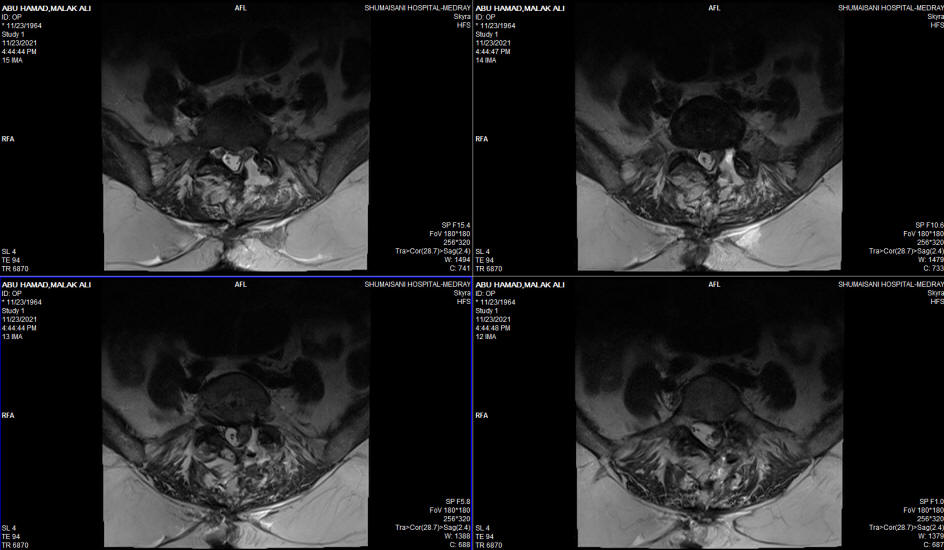

23-NOVEMBER-2021  MALAK ALI ABU-HAMD  57 YEARS CONDITION AFTER DISCECTOMY L5-S1 WITH POSTOPERATIVE ALMOST FLAIL LEFT FOOT.

The patient came to the clinic 13-November-2021 with flail left foot with back-slap applied to her left foot after performed surgery for PLD L5-S1 2 weeks ago elsewhere. The condition deteriorated immediately after surgery. The patient underwent surgery 11 years ago for PLD L5-S1 left side and MRI done before the last surgery showing medium size extrusion L5-S1 with extradural compression left side. MRI done 10-November-2021 after surgery showing the extrusion penetrating the dura and intradurally compressing the roots. Dynamic studies ruled out overmobility. She is a known hypertensive for 9 years in treatment.

The level of L5-S1 was identified by the C-arm. Extended foraminotomy left S1 root with removal of compressing elements. The extruded disc was removed in several tiny pieces to avoid sudden onset CSF leak, After that the disc disc of L5-S1 was cleaned from the left side. Using Omnipaque 10 cc, myelography was used to rule out presence of intradural piece. By the the C-arm the data were negative. Intraoperative MRI was not achievable due to technical problem with the docking system of the Skyra. Using MultiGen, bipolar stimulation of the left S1 root was achieved with 2.8 Volts. A bipolar pulsed mode RF with 42 Celsius, 240 sec, 2 Hz and 20 msec duration to the left S1 root  was achieved using 2 bended catheters 10 mm exposed length. Further bipolar stimulation of the left S1 root was achieved with 2.0 Volts. The patient was put in Reverse Trendelenburg position with Valsalva maneuver and hyperventilation. No CSF leak. A fat tissue with pedicle was used to cover the dura to minimize the postoperative scar formation and prevent postoperative CSF leak. Routine closure of the wound. Smooth postoperative recovery. The power of the left foot improved slightly. She was sent to the ward.

Immediate post-operative MRI showing the ugly old scar at the operative site and MR Myelography ruling out intradural disc material.

Location of the scar above the axilla. The root is free and lax.